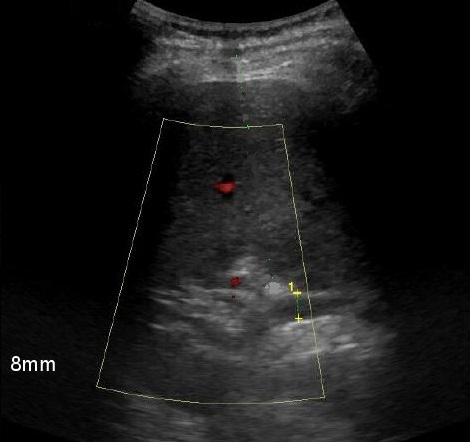

Dilatation de voie

biliaire intrahepatique avec sa diametre de

depasse 8mm . Image echographie percutane en

Doppler de voie biliaire dilate , il y n'a

pas de flux Doppler en couleur

de voie biliaire , cela peut

permet de diffencie avec image de flux en

color des vaisseaux hepatiques

. Cholangite aigue des voies biliaires |